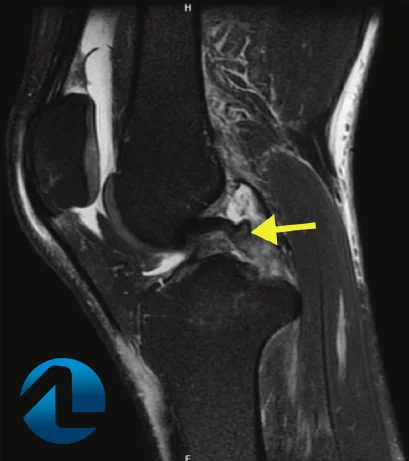

O exame de escolha para o diagnóstico é a ressonância nuclear magnética da perna, que freqüentemente mostra o espessamento do periósteo da região da dor. O principal diagnóstico diferencial desta lesão é a fratura de estresse, observada na ressonância magnética, cintilografia óssea de 3-fases e radiografias simples.